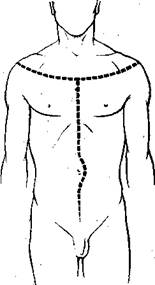

Этот метод применяют в тех случаях, когда хотят сохранить кожу шеи целой. Он состоит в том, что сначала проводят поперечный разрез кожи гру-ди, начиная его слева на три пальца ниже acromion лопатки, и заканчивают симметрично на правой стороне. Разрез проводят дугообразный, вогнутостью обращенный к шее и проходящий через срединную линию на уровне вторых межреберных промежутков (рис. 28).

От середины этого разреза проводят обычный основной разрез- до лобка.

| Рис. 28. Разрез по методу Лешке. |

Начиная от середины разреза по методу Лешке, отсе-паровывают кожу шеи с подкожной клетчаткой, оттягивая ее кверху. При этом обнажается верхняя часть грудины, ключицы и все органы шеи до нижней челюс-: ти. При извлечении органов

шеи работать приходится под кожным лоскутом, оттягивая его, чтобы случайно не прорезать кожу изнутри.

Преимущество этого способа состоит в том, что при нем открывается широкий доступ к подмышечным впадинам и плечевым суставам.

Недостатком является некоторая трудность манипуляций под лоскутом.